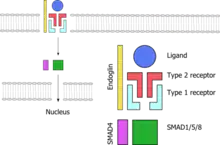

All genes known so far to be linked to HHT code for proteins in the TGF-β signaling pathway. This is a group of proteins that participates in signal transduction of hormones of the transforming growth factor beta superfamily (the transforming growth factor beta, bone morphogenetic protein and growth differentiation factor classes), specifically BMP9/GDF2 and BMP10. The hormones do not enter the cell but link to receptors on the cell membrane; these then activate other proteins, eventually influencing cellular behavior in a number of ways such as cellular survival, proliferation (increasing in number) and differentiation (becoming more specialized).[1] For the hormone signal to be adequately transduced, a combination of proteins is needed: two each of two types of serine/threonine-specific kinase type membrane receptors and endoglin. When bound to the hormone, the type II receptor proteins phosphorylate (transfer phosphate) onto type I receptor proteins (of which Alk-1 is one), which in turn phosphorylate a complex of SMAD proteins (chiefly SMAD1, SMAD5 and SMAD8). These bind to SMAD4 and migrate to the cell nucleus where they act as transcription factors and participate in the transcription of particular genes. In addition to the SMAD pathway, the membrane receptors also act on the MAPK pathway, which has additional actions on the behavior of cells.[2] Both Alk-1 and endoglin are expressed predominantly in endothelium, perhaps explaining why HHT-causing mutations in these proteins lead predominantly to blood vessel problems.[2][8] Both ENG and ACVRL1 mutations lead predominantly to underproduction of the related proteins, rather than misfunctioning of the proteins.[8]